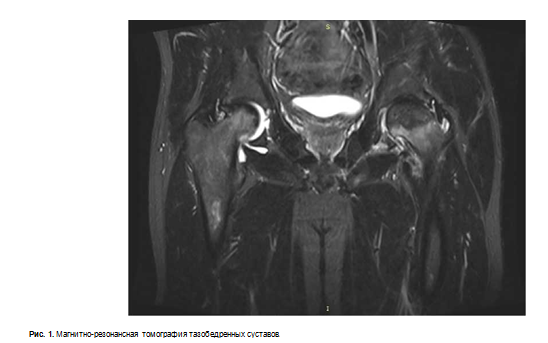

С целью дообследования выполнена магнитнорезонансная томография тазобедренных суставов (рис. 1).

Учитывая клинические проявления (болевой синдром, нарушение функции правой нижней конечности, отсутствие опорности из-за выраженного болевого синдрома), рентгенологические данные (асептический некроз головки бедренной кости справа) выставлен диагноз правосторонний асептический некроз головки бедренной кости, что является показанием к оперативному лечению.